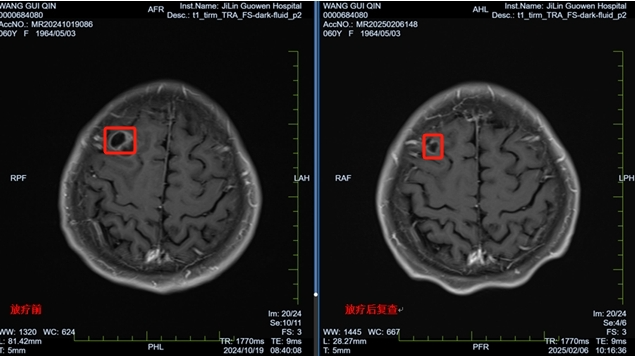

60歲的王阿姨(化名)是一位肺癌患者,通過(guò)積極規(guī)范治療已進(jìn)入疾病穩(wěn)定期,4個(gè)月前的一個(gè)早晨出現(xiàn)頭暈伴有劇烈的頭痛,進(jìn)而出現(xiàn)惡心嘔吐,這讓王阿姨感到恐慌,當(dāng)日及時(shí)來(lái)到我院就診,檢查頭顱核磁結(jié)果確診為肺癌腦轉(zhuǎn)移且伴有明顯的腦水腫,王阿姨一度陷入絕望。耿光三主任的及時(shí)心理疏導(dǎo)和勸說(shuō),讓她了解到放療是治療腦轉(zhuǎn)移的有效手段,并抱著一線希望接受了治療。

針對(duì)王阿姨腦轉(zhuǎn)移的情況,耿光三主任帶領(lǐng)團(tuán)隊(duì)精心制定了治療方案,給予緩解腦水腫等對(duì)癥治療,針對(duì)多個(gè)位置的大小不等的腦轉(zhuǎn)移灶,設(shè)計(jì)了分次立體定向放療(FSRT)技術(shù)進(jìn)行高劑量照射,精準(zhǔn)打擊腫瘤。

經(jīng)過(guò)一個(gè)療程的放療,王阿姨的頭痛、惡心等癥狀明顯緩解,精神狀態(tài)好轉(zhuǎn)。本次復(fù)查結(jié)果顯示,腦部腫瘤明顯縮小,病情得到有效控制。王阿姨重新燃起了對(duì)生活的希望,樂(lè)觀面對(duì)未來(lái)。